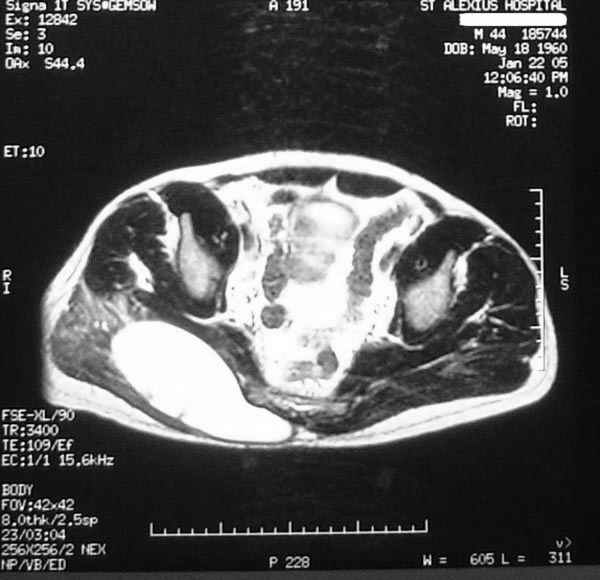

Уважаемые коллеги,Неоднократные пункционные эвакуация (3 раза) крови изягодичной области, после полученной пройзводственнойтравмы (более 1.5 мес) ударом в ягодицу тяжелым, около полутонны предметом.

Рентгенограмма без особенностей, несмещенные переломы лонной и седалищных костей таза.Последная пункция 10 дней назад 180 мл темной крови, после пункции сделано магнито-резонансные исследование (на снимках), какой диагноз и тактика дальнейшего лечения, какие рекомендации?Джолдас Кульджанов

Разбираемый случай немного отличался от классического Degloving Injury

или Morel-Lavalle Lesion, которые часты при переломах ацетабулума и

костей таза. Состояние, наблюдаемое после удара, в результате чего

образуются обширные полости в тазобедренной области: ягодицы или

большого вертела. Как описал Анатолий, обширные полости заполняются

кровью, затем синовиальной жидкостью, отодвигают сроки операции или

после операции приводят к осложнениям послеоперационных ран.

Описанный случай:

В промежутке около месяца 3 пункции с удалением около 180 мл крови

каждый раз. После исследовании МРТ было принято решение - удаление

гематомы в операционной более широким доступом. Во время операции -

под ягодичной мышцей была капсула, где скопилось около 700 мл

гематомы, после удаления в полости обнаружили несколько закупорившихся

вен и краевой разрыв одной из двух ветвей нижней ягодичной артерии.

После промывания, гемостаза и дренажа, по рекомендации хирурга стенку

полости обработали спреем Tisseel, специальным склерозирующим

препаратом, применяемым пластическими хирургами, затем зашили рану.

Дренажи удалены на 5 день, рана зажила первично. Случай был интересен

применением препарата Tisseel Fibrin Sealant для склерозирования

полостей, только недавно получившим разрешение к применению, хотя по

аннотации в Европе и в Южной Америке применяют давно.